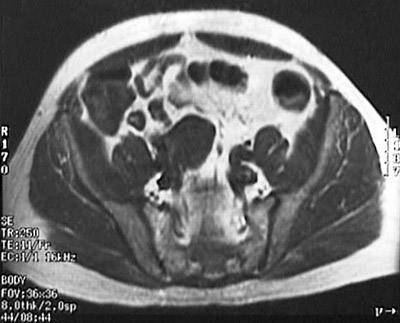

| Here is an unusual location with an unusual name, but it is part of the extra-adrenal paraganglion system and can be a site for the 10% of pheochromocytomas that are extra-adrenal. These MRI scans in coronal view above and axial view below demonstrate a pheochromocytoma of the organ of Zuckerkandl located just below and to the right of the aortic bifurcation. |